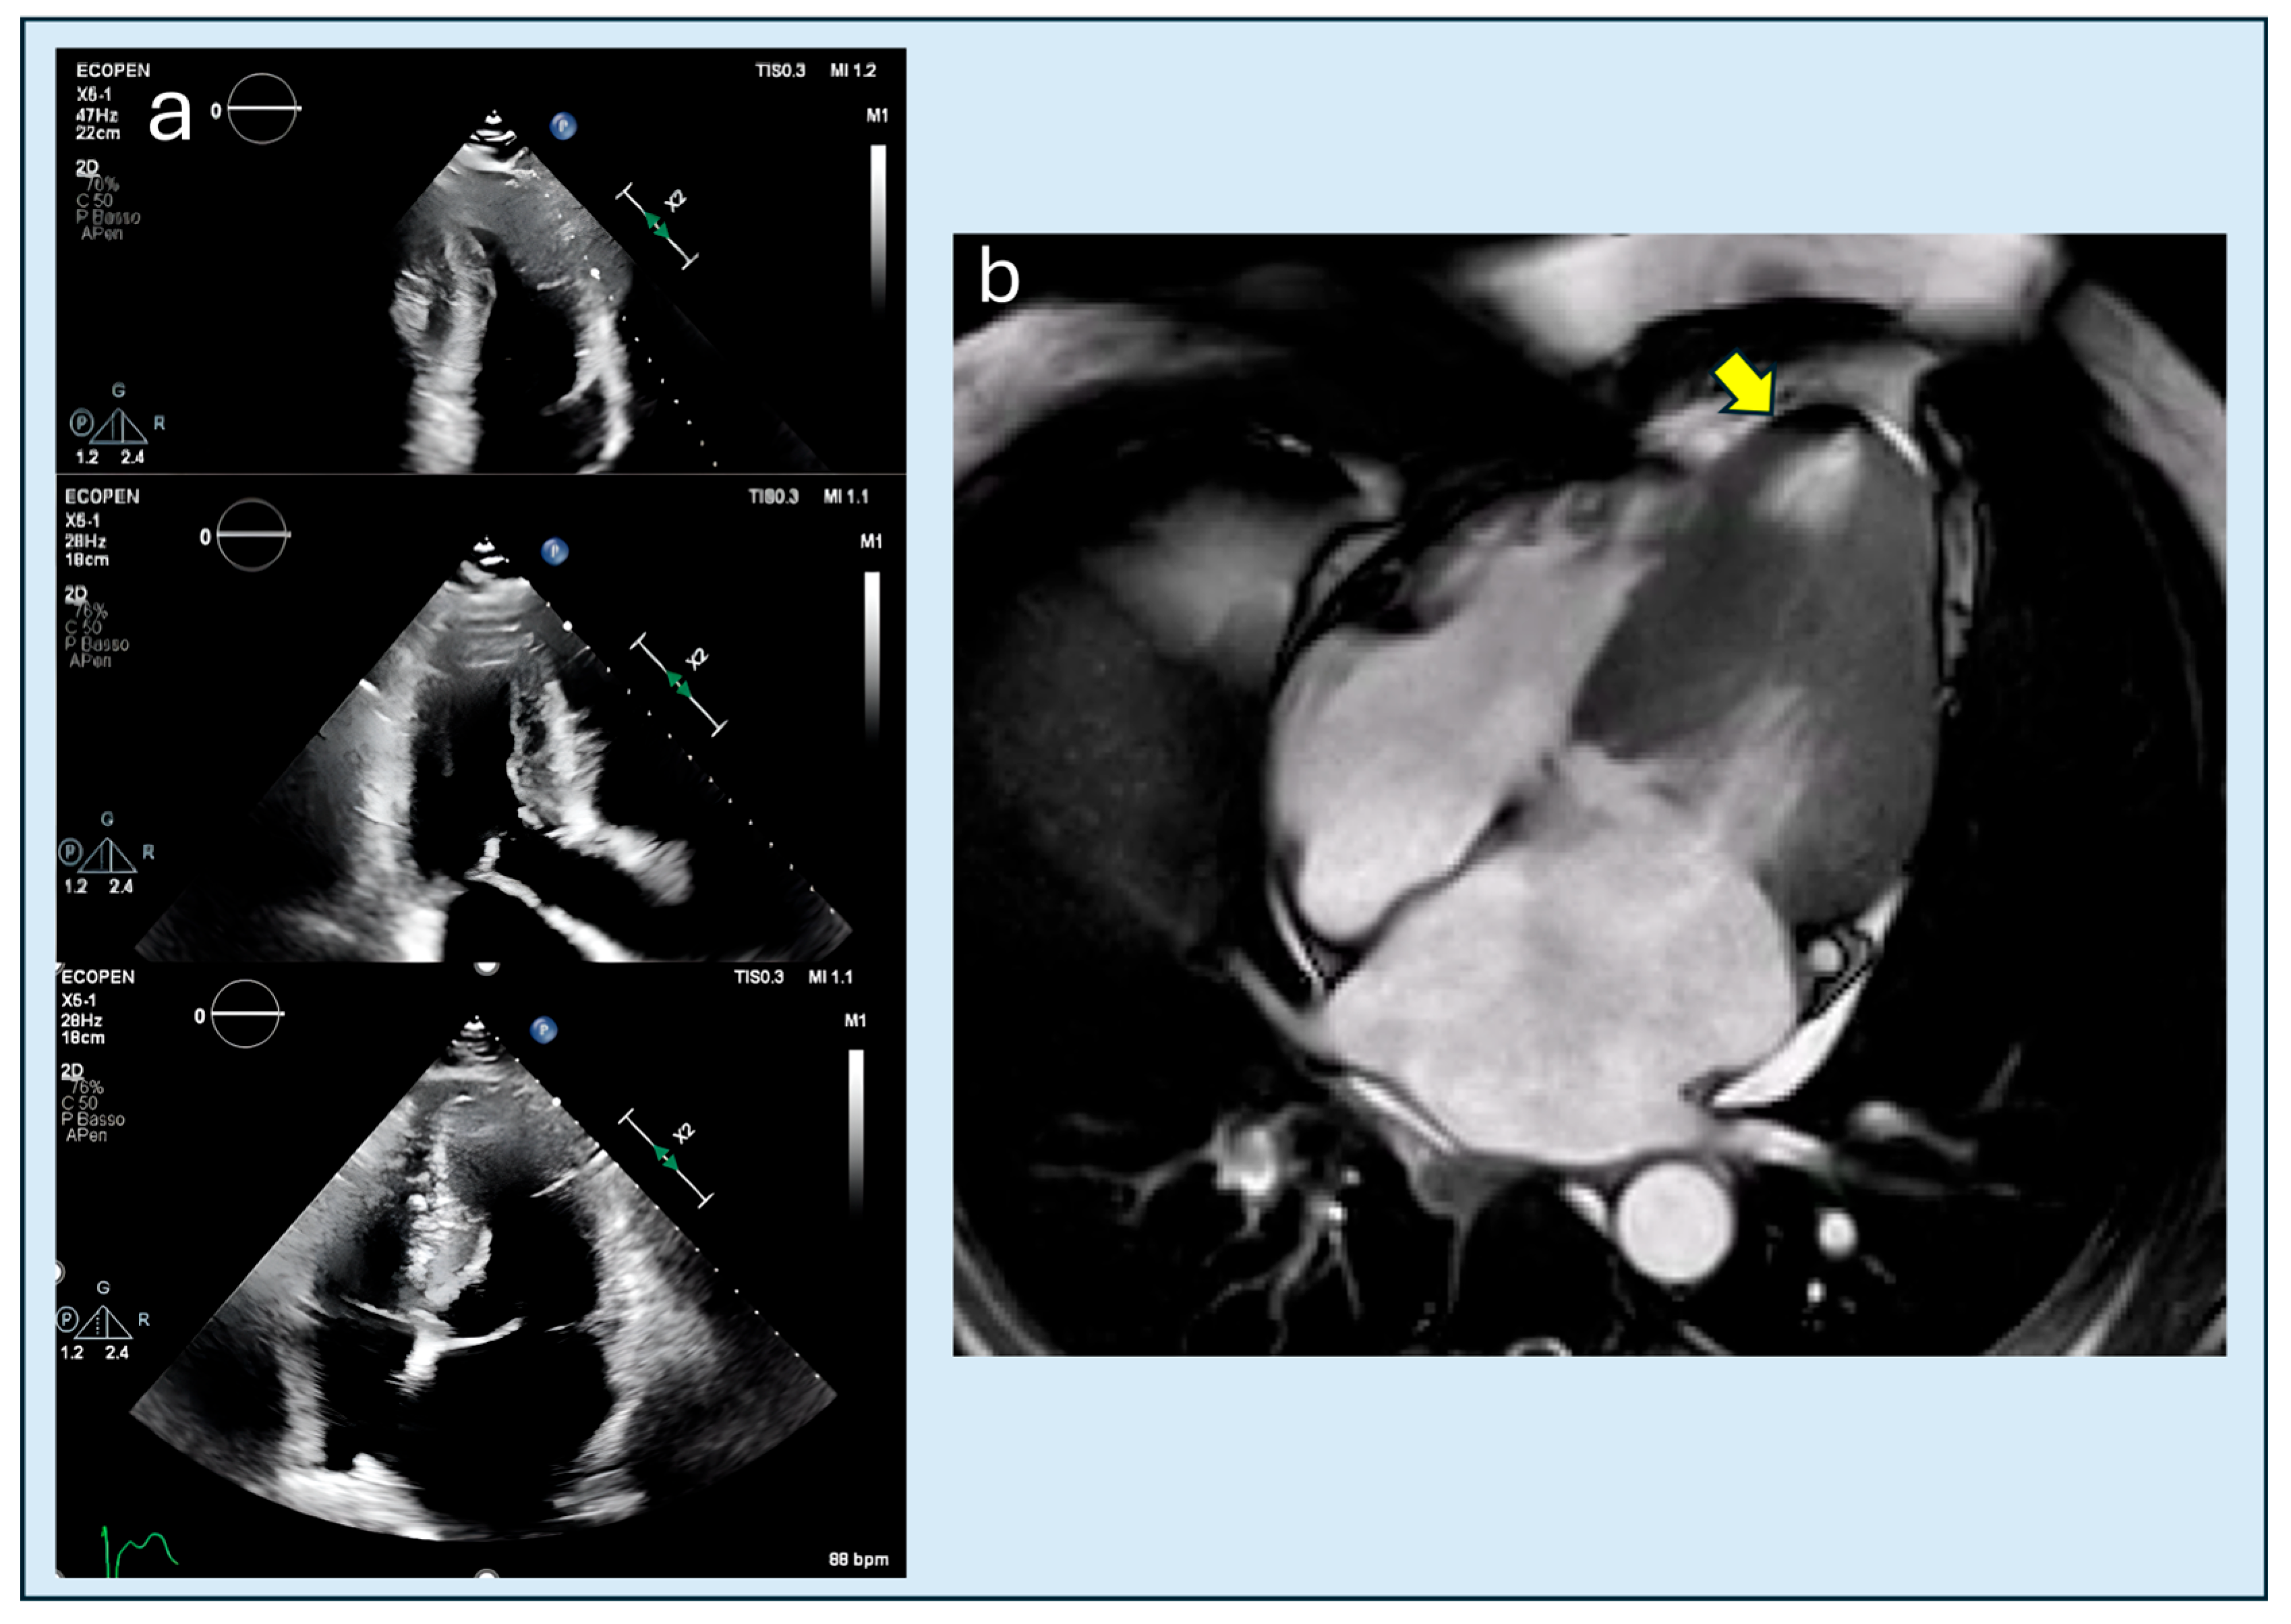

| Echocardiographic Detection | Good sensitivity, especially for septal hypertrophy; color-Doppler useful for LVOT obstruction | Often underestimated without contrast; up to 43% of apical aneurysms may be missed by TTE |

| Apical cavity obliteration severity | TTE/CMRi | End-systolic closure | Echo/CMR cohorts | Prognostic | Moderate | +++ | Hamza 2025 [20] |

| Apical aneurysm detection | CMRi→TTE | Dyskinesis + scar | CMR aneurysm cohorts | Echo misses 43% | High | + | Hamza 2025 [20] |